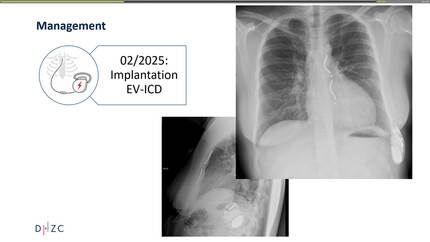

The heart beneath the sternum: a case of ventricular arrhythmia in pectus excavatum